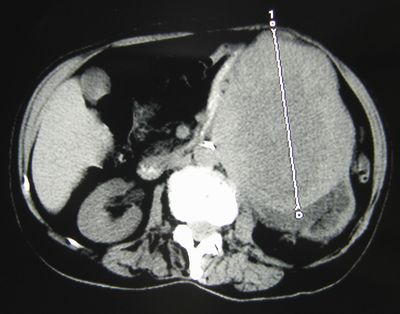

Опухоль левой почки больших размеров